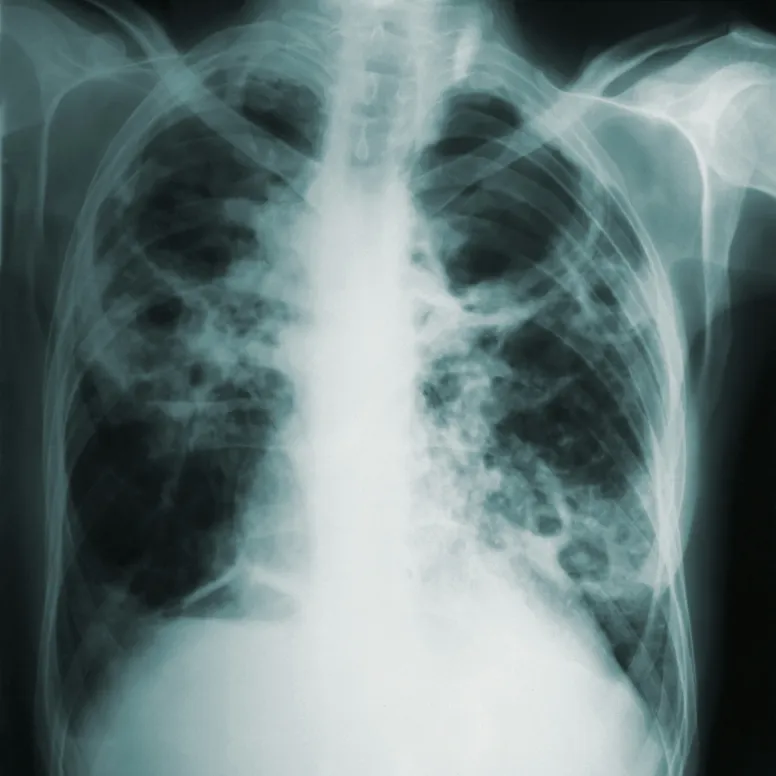

Black lung disease, also known as coal workers' pneumoconiosis, is a serious respiratory condition that affects miners exposed to coal dust over an extended period. The primary cause of black lung disease is the inhalation of coal dust particles that accumulate in the lungs and cause inflammation and scarring.